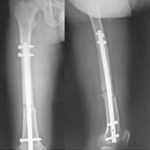

張某,男,50歲,因“左股骨骨不連”入院。植骨+PRP治療后8月完全愈合。

術前

術中

術后完全愈合